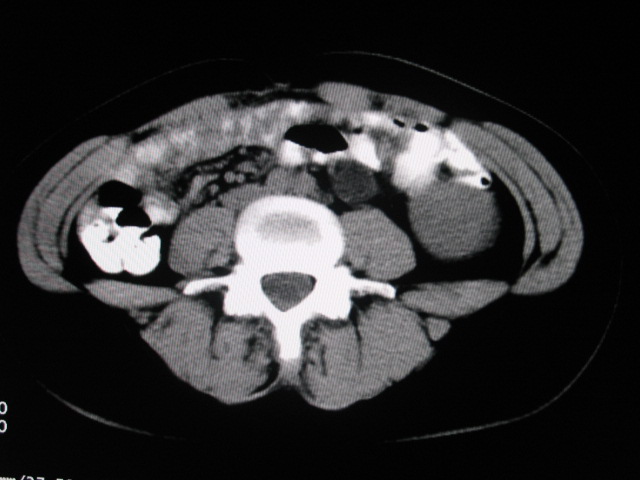

女,28岁,自觉腹部包块一年余

左侧为扩张的输尿管,一直延续到膀胱,那么它的上端应该是扩张的肾盂,但是在他的下方我们看到一个比较正常的肾,所以考虑左侧重复肾盂输尿管畸形。

考虑左侧双肾盂双输尿管畸形,其中一输尿管末端梗阻(不排除异位开口可能)并相应之肾盂及输尿管明显扩张积水。

左侧重复肾、双输尿管畸形。重复肾一般上位肾发育不良,易合并积水。

考虑左侧双肾盂双输尿管畸形,其中一输尿管末端梗阻(不排除异位开口可能,不知病人有无不自觉溢尿,有可能开口于阴道或宫颈,也可下端为盲端)并相应之肾盂及输尿管明显扩张积水。

术后证实是左侧双肾盂双输尿管畸形,巨输尿管巨肾盂症